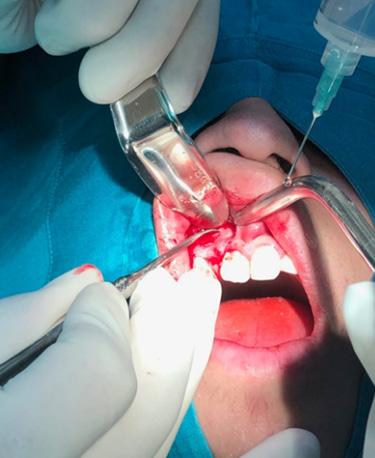

Aplicación de biomateriales post exeresis en un quiste inflamatorio radicular

Application of biomaterials post exeresis of a root inflammatory cyst

Javier Adrián Burgos, Renia Hurtado, Fabián Galindo, Juan Delgado....................................................97-106